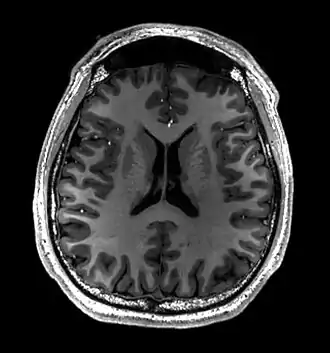

![]() Cross-sectional T1-weighted MRI of a healthy human brain acquired with an ultra high-field MR of 7 Tesla field strength | |

Magnetic resonance imaging of the brain uses magnetic resonance imaging (MRI) to produce high-quality two- or three-dimensional images of the brain, brainstem, and cerebellum without ionizing radiation (X-rays) or radioactive tracers.

- T1-weighted (T1W) images: Cerebrospinal fluid is dark. T1-weighted images are useful for visualizing normal anatomy.